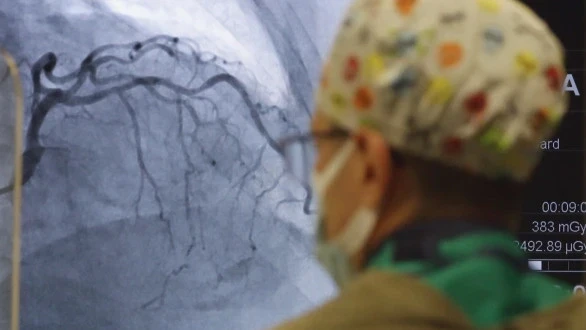

Сердечно-сосудистые заболевания (ССЗ) продолжают оставаться основной причиной смертности в стране. В 2021 году они составили 52% от общего числа летальных случаев, при этом более 80% смертей были связаны с неинфекционными заболеваниями, что особенно затрагивает трудоспособное население.

Чтобы справиться с этой проблемой, Национальный центр кардиологии разработал интегрированную модель профилактики, которая включает в себя самоконтроль по восьми критериям здоровья: курение, питание, физическая активность, индекс массы тела, артериальное давление, уровень холестерина, сахара и качество сна.